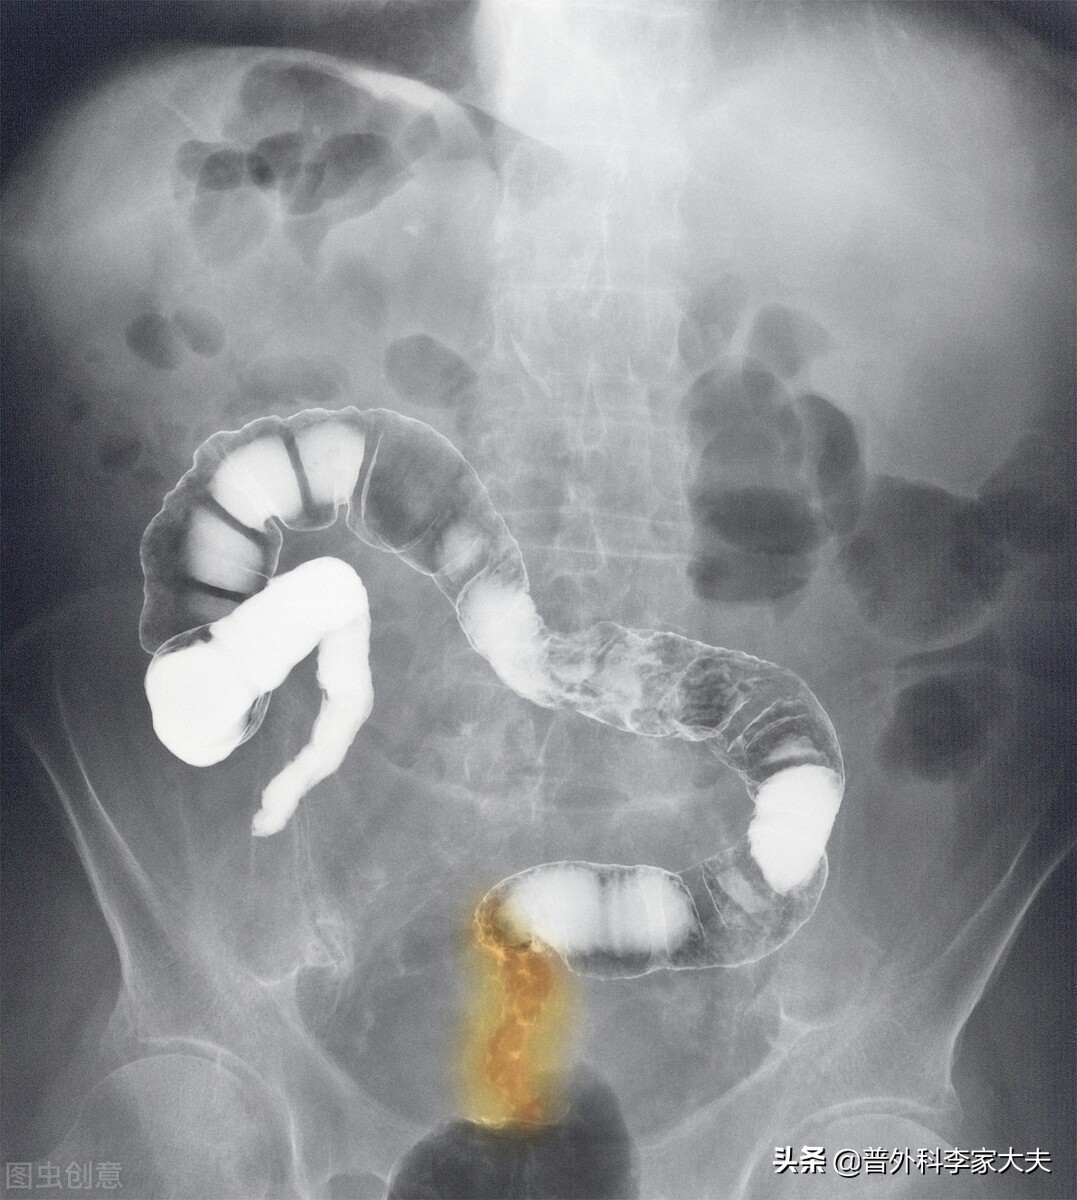

结直肠吻合口是结肠与直肠或肛门两侧断端用机械方法吻合在一起愈合形成的。要让机械吻合在一起的肠管断端愈合如正常肠管,则首先要保证吻合上下两断端肠管的血运要好,血运好,才能保证促进断端伤口愈合的营养供应要良好。吻合操作时,如果上下两断端肠管的血管条件良好,留置吻合肠管长度适宜,有经验的胃肠专家按正确的吻合器操作方法进行吻合,一般不会出现因技术操作造成的吻合口漏发生。但手术当时没事,不代表术后就没事。如果术后患者出现贫血等身体不好因素,加上营养供给不足的话,则会导致吻合口愈合不良而发生术后吻合口瘘。另外,由于低位直肠癌做保肛手术后,结直肠恢复成闭袢性肠管的解剖特点,于是当患者进食后,食物残渣形成的粪便,以及进食后因各种原因导致肠道内产生气体,会使得脆弱的吻合口接受张力的考验,并且随着吻合口张力的增加,也必然会影响吻合口局部的血运不佳,结果也是会影响吻合口愈合,最后导致吻合口瘘发生。

预防性回肠造口,会让大量的食物残渣与吞入产生的气体由造口流出来,于是进入结肠内的食物残渣与气体就会大大减少,由此自然有助于减轻吻合口的张力,有利于吻合口的愈合,从而减少吻合口瘘的发生。

低位直肠癌保肛手术后,形成的闭袢性肠管的解剖特点,经及结肠储存粪便与直肠高压排便的生理功能,加上吻合口早期愈合不牢靠,才是导致吻合口瘘发生的原因。因此,只要让患者粪便不储存无压力排出,则可避免吻合口瘘发生。我的方法是于肛门处放置大号硅胶弹性肛管十天左右时间。排便时,硅胶弹性肛管会随大便脱落,可通过肛镜重新放置。从我目前治疗的大量低位直肠癌患者情况分析,是能取代预防性回肠造口来避免术后吻合口瘘发生风险的。目前这一技术也在周边城市医院得到推广,从近几年的临床研究反馈还是不错的。